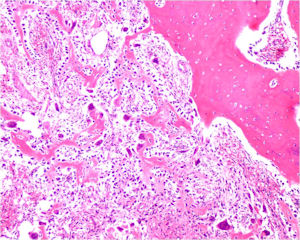

Gross Pathology

The gross pathology of an osteoblastoma is indistinguishable from an osteoid osteoma except larger

- Nidus is well demarcated

- Granular, friable, reddish hemorrhagic tissue

- May bleed significantly when curetted

- Cortex is thinned, possibly destroyed

Microscopic Pathology

- Interlacing network of bone trabeculae in a loose fibrovascular stroma

- Prominent vessels

- Osteoblasts are plump, active, scattered mitotic figures

- Osteoblasts line up around periphery of trabeculae (Osteoblastic Rimming)

- Soft tissue component usually surrounded by shell of reactive bone or periosteum (Egg Shell Rim of Calcification)

- No cartilage production (as opposed to osteosarcomas that may contain areas of cartilage)